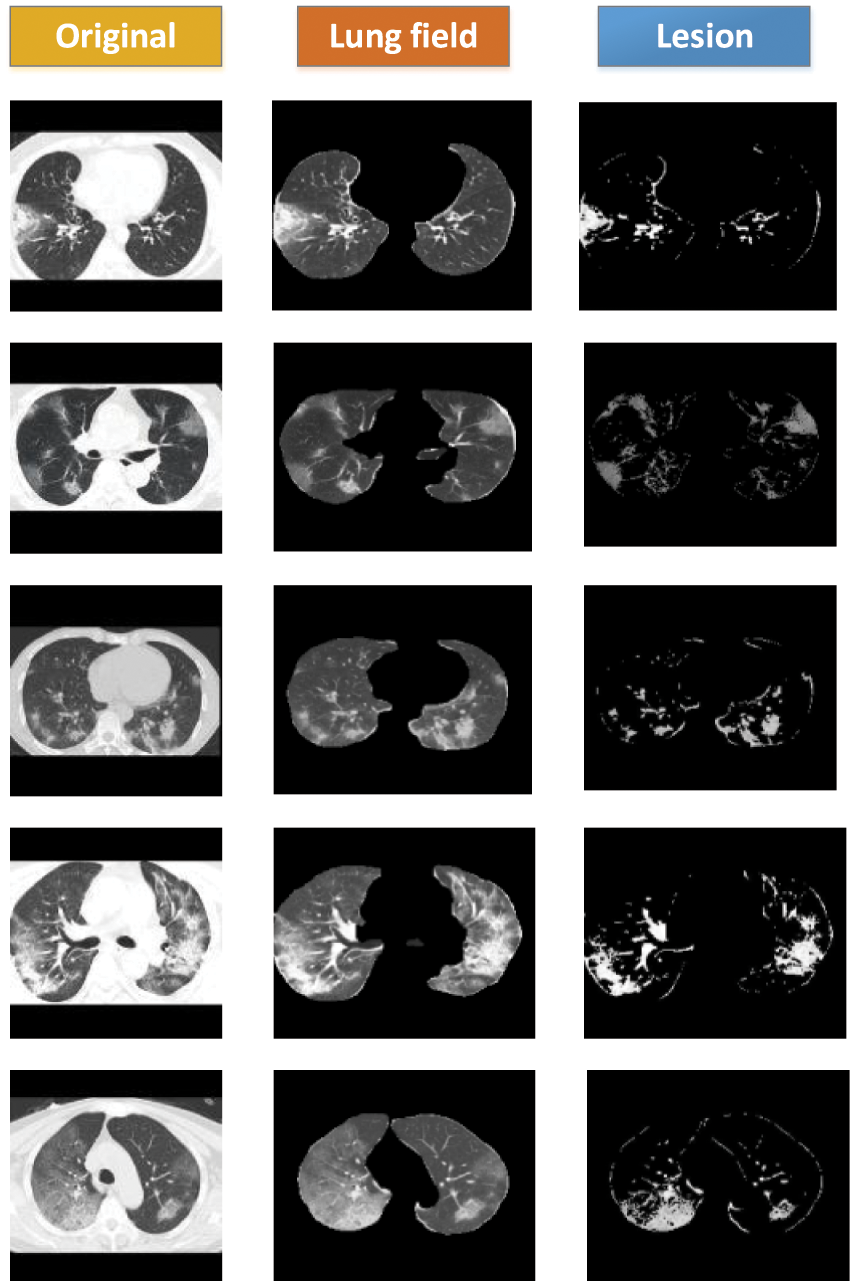

4.5 FCM Clustering Visualization Results

The data used in this study were image-level markers and could only be used for classification; no focal areas were marked. We used the FCMM to view the size and location of the lesions. Fig. 9 contains three sets of images: the first set contains the original images (Data 1), the second set contains the images after segmenting the lung area using weak supervision (Data1-P), and the third set contains the images of the lesion area using FCM. The lesions could be viewed, and FCMM was effective.

Figure 9: FCM clustering visualization showing COVID-19 lesion results